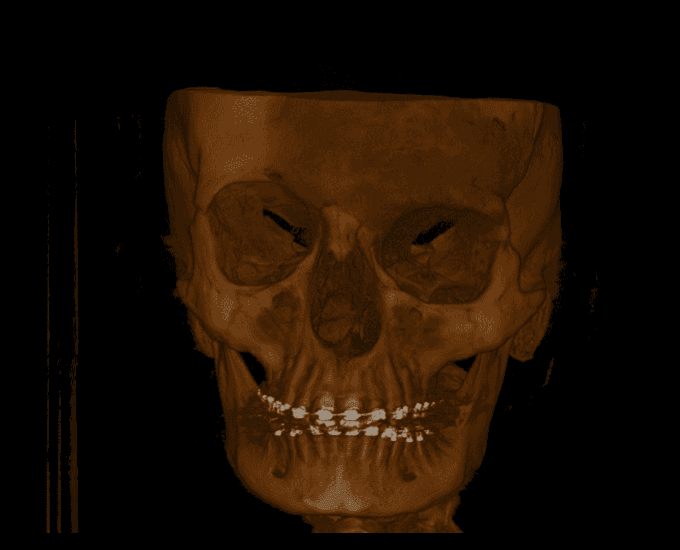

Any CT scans

Volume example 1 Volume example 2 Volume example 3 Volume example 4 Volume example 5 Volume example 6